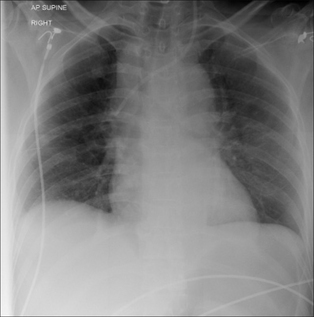

QUESTION 2—IS THERE A PNEUMOTHORAX?

Following violent trauma the CXR is obtained with the patient lying on a trolley or examination couch. A large pneumothorax will be obvious. Smaller pneumothoraces are more difficult to detect on a supine CXR. Recognising a small pneumothorax is important—particularly if the patient is to be treated with positive pressure ventilation.

The features indicating a pneumothorax on a supine CXR are described in Chapter 7, pp. 97–100.

image

Figure 32.8 Pneumothorax. When the injured patient is lying supine, air in the pleural space collects at the highest point—i.e. anteriorly (a). On the frontal CXR the visceral pleural line may not be evident. The diagnosis will need to be made by scrutinising the areas around the dome of the diaphragm and adjacent to the lateral border of the heart (b). The black line outlining the diaphragm indicates a pneumothorax: see p. 97 for a detailed description.